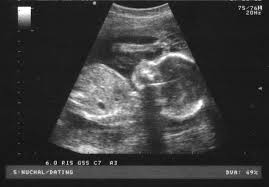

It was Saturday and I had an appointment with my doctor. It

was my fifth month and doctor had called me for ultrasound to find out the

growth and placement of baby. I had a mixed feeling. I was happy and curious

and yet nervous because I was going to know about my baby and would get his

first glimpse. I was just praying to God that everything should be fine and my

fastest as far as I could remember. After the process of 10 minutes, finally I was

told that my baby was absolutely fine and healthy. And then doctor showed me the ultrasound

pictures. I was still and mum looking at it, It was unbelievable, I was seeing

my baby who was inside me……….Oh My God……it was just amazing. And then I realized,

tears had rolled down my cheeks. My husband was with me. We both were overwhelmed

with joy.